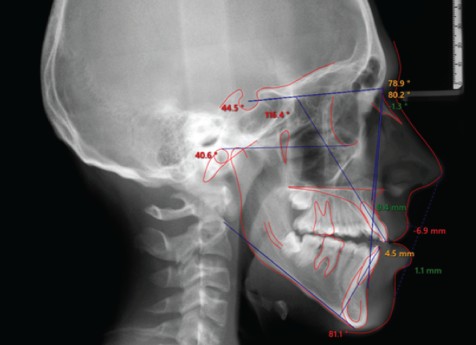

A. 세팔로 방사선 사진과 기도 분석, 구강 근기능 검사 등을 통해 구호흡과 부정교합의 연관성을 평가할 수 있습니다. 상악 협착, 개방교합, 수직 성장 패턴 등이 동반된 경우 구호흡의 기여도가 높을 수 있으며, 정밀 검사 후 치료 방향을 안내해 드립니다.

장기간 구호흡을 지속한 경우, 수직 안면 성장 패턴이 우세해지면서 긴 안모(long face syndrome), 하악 후퇴, 상악 돌출 등의 골격 변화가 동반될 수 있습니다. 이는 성장이 완료되기 전 기능 개선 개입의 필요성을 뒷받침합니다.

구호흡이 성장기 내내 지속되면 안면 골격 자체의 성장 방향에도 영향을 줄 수 있습니다. 수직 성장 패턴이 강해지면서 긴 안모, 하악 후퇴, 상악 전돌이 동반되는 경우가 이에 해당합니다. 골격 변화는 성장이 완료될수록 교정만으로 접근하기 어려워지므로, 성장기에 조기 발견하는 것이 중요합니다.